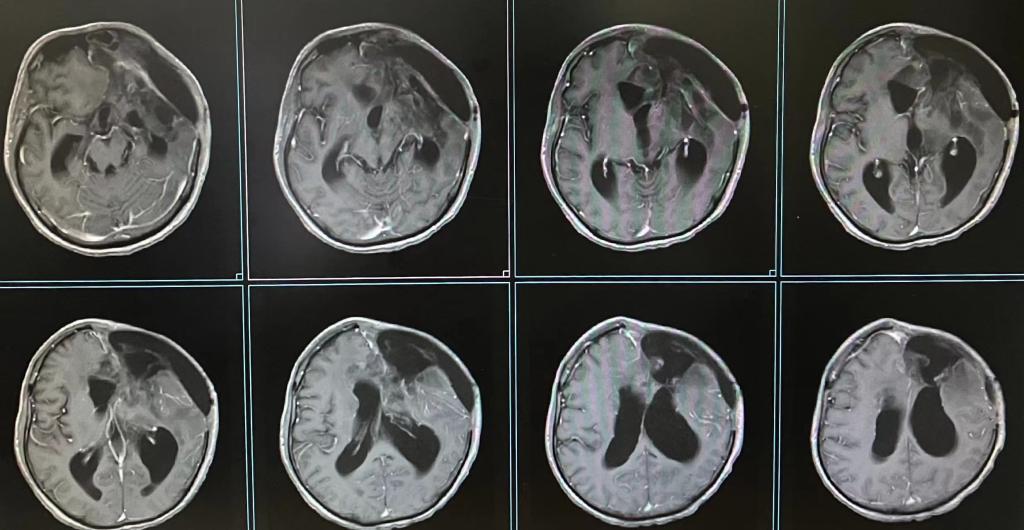

患者术后头颅MRI

术前潘先生右侧肢体已失去了大部分活动能力,因肿瘤已将功能肢体功能破坏,术后功能无法恢复,面对这样的结果,潘先生及家属显得格外乐观和坚强。潘先生的母亲对池超超副主任医师说:“我相信你们已经作出了最大的努力,我非常信任你们为我儿子作出的抉择,接下来我们一定会积极治疗,不会辜负你们为他延续了两次生命。”

手术后不久,潘先生转入肿瘤科进行规范化的放化疗等,经过3个月治疗后,潘先生转入康复医学科行康复治疗,复查头颅MR未见明显肿瘤病灶。